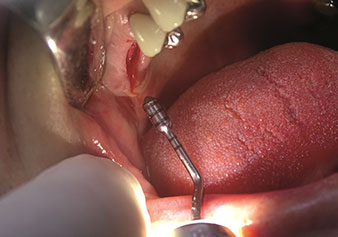

Sinus lift par voie crestale

W&H propose également la solution idéale pour le sinus lift par voie crestale.

Après la préparation des sinus maxillaires à l'aide du jeu d'inserts correspondant (Fig. 3), le nouvel insert Z35P (Fig. 4) est utilisé pour l’élévation de la membrane par technique hydrodynamique. Le même jeu d'inserts peut aussi être utilisé pour la préparation piézochirurgicale du lit implantaire en augmentant les diamètres (Figures 3 et 4 fournies avec l'autorisation du Dr Mario Kirste, Francfort-sur-l’Oder).